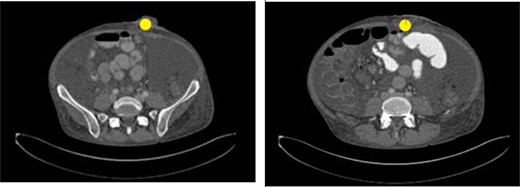

Prior to the index presentation, the patient presented to the emergency department with generalized weakness and blood per rectum for 2 weeks. He had no changes in diet, but endorsed intermittent abdominal discomfort, as well as increasing anal pain and drainage. The only abnormality on digital rectal examination was minor peri-rectal excoriation. Computed tomography CT imaging (Fig. 1) shows significant ascites, a non-obstructing mass at the base of the mesentery rectum, mesenteric adenopathy and dilated loops of small bowel. There were no signs of obstruction or abdominal distension. Evaluation under anesthesia demonstrated a large, firm indurated necrotic mass above the dentate line forming a malignant fistula to the perianal skin. There was also thickening of the perianal skin circumferentially that was likely secondary to chronic irritation from fistulous drainage or pagetoid spread of a malignancy. Biopsy results revealed poorly differentiated invasive squamous cell carcinoma with extensive necrosis. Left and right lateral perianal skin showed focal severe squamous dysplasia and high-grade squamous dysplasia, respectively. Ultimately, the diagnosis of stage T3N0M0 squamous cell carcinoma of the anus was made.

CT abdomen and pelvis with IV contrast showing an ill-defined mass at the root of the mesentery measuring at least 5.2 × 5.1 cm (yellow circle). This was hypothesized to represent conglomerate lymphadenopathy, a potential neoplasm, such as mesothelioma or lymphoma, or metastatic disease. There was also a large volume of abdominal ascites and mildly dilated loops of small bowel within the left abdomen which likely represented a partial obstruction or ileus.